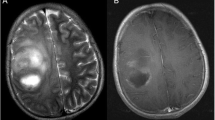

Comparison of cystic malacia with cavernous angioma and white matter degeneration in the same patient group (Fig. 4) revealed that the incidence of cavernous angioma after high-dose cranial irradiation increased progressively, while that of cystic malacia did not increase after 5 years. White matter degeneration developed earlier than cystic malacia or cavernous angioma. Development of these three entities was mutually exclusive, and there was no association between the site of occurrence of cystic malacia and that of white matter degeneration or cavernous angioma. Representative cases are shown in Fig. 5a–c.

a A boy with a left temporal primitive neuroectodermal tumor who underwent chemoradiotherapy at the age of 10.9 years. MR examination 28 months later revealed cystic malacia on axial T2-weighted images (left side panel). He also had multiple secondary cavernous angiomas (right side panel). b A pediatric patient with left temporal anaplastic astrocytoma who underwent radiotherapy at the age of 4.2 years. MR examination 24.5 months later revealed cystic malacia on axial T2-weighted images. Subsequently, he developed seizure and needed anticonvulsants for seizure control. He did not have secondary cavernous angioma at the follow-up period of 56.5 months. c A pediatric patient with pineoblastoma who underwent radiotherapy at the age of 7.6 years. MR examination 42.0 months later revealed cystic malacia at right cerebellum and right parietal deep white matter on axial T2-weighted images (left side panel). He also had multiple secondary cavernous angiomas (right side panel)